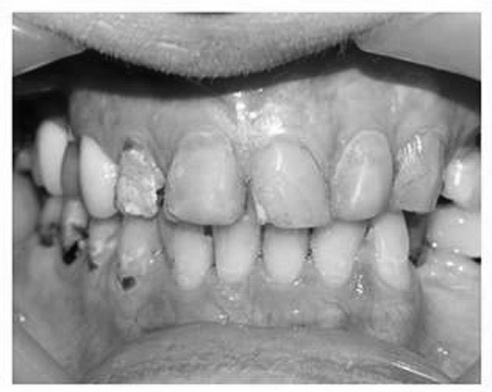

| Răng trước khi điều trị. |